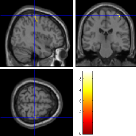

Once the reduced FOV images are available, the proposed pMRI 4D-UWR-SENSE algorithm and its early UWR-SENSE version have been utilized in a final step to reconstruct the full FOV EPI images and compared to the mSENSE Siemens solution. For the wavelet-based regularization, dyadic Symmlet orthonormal wavelet bases [48] associated with filters of length 8 have been used over resolution levels. The reconstructed EPI images then enter in our fMRI study in order to measure the impact of the reconstruction method choice on brain activity detection. Note also that the proposed reconstruction algorithm requires the estimation of the coil sensitivity maps (matrix in Eq. (2)). As proposed in [4], the latter were estimated by dividing the coil-specific images by the module of the Sum Of Squares (SOS) images, which are computed from the specific acquisition of the -space centre (24 lines) before the scans. The same sensitivity map estimation is then used for all the compared methods. Fig. 5 compares the two pMRI reconstruction algorithms to illustrate on axial, coronal and sagittal EPI slices how the mSENSE reconstruction artifacts have been removed using the 4D-UWR-SENSE approach. Reconstructed mSENSE images actually present large artifacts located both at the centre and boundaries of the brain in sensory and cognitive regions (temporal lobes, frontal and motor cortices, …). This results in SNR loss and thus may have a dramatic impact for activation detection in these brain regions. Note that these conclusions are reproducible across subjects although the artifacts may appear on different slices (see red circles in Fig. 5). One can also notice that some residual artifacts still exist in the reconstructed images with our pipeline especially for . Such strong artifacts are only attenuated and not fully removed because of the high level of information loss at .

| mSENSE | 4D-UWR-SENSE | ||